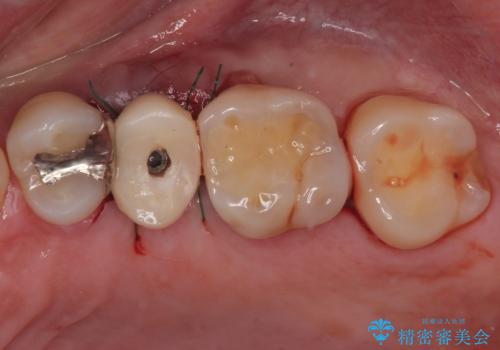

- むし歯で抜歯したまま放置していたとのことで来院された患者様です。

仕事が忙しいことと、外科手術が怖いとのことで歯科医院を避けていたものの、当院の1DAYインプラント治療を見て、重い腰を上げて来院されたとのことでした。

事前に仮歯を用意し、インプラント埋入時に仮歯を装着し、その後歯肉の治りを待って速やかにオールセラミッククラウンにて補綴治療を行うこととしました。

インプラント埋入時に十分な安定性が確認できたため、当日仮歯を装着しました。